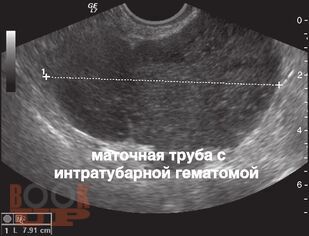

Учебно-методическое пособие посвящено вопросам диагностики и лечения внематочной беременности. Авторами составлены учебнометодические рекомендации, позволяющие в максимально короткие сроки установить диагноз внематочной беременности и выполнить соответствующий объем оперативного вмешательства. Представлены современные методы лечения при различных локализациях внематочной беременности, в том числе и редких форм.